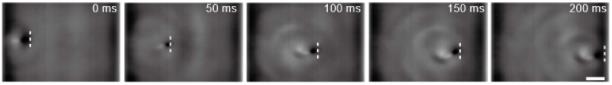

在静态环境实验取得了满意的测试结果后,研究人员开始了机器鱼的“逆行”之旅:

磁驱软体鱼在细管中的逆游性能

如图中所示,当磁场的振荡角为40°时,磁驱软体鱼的最大速度达到13cm/s(水流速度5cm/s),而水流速度加到10cm/s时,可以达到4cm/s的游泳速度。